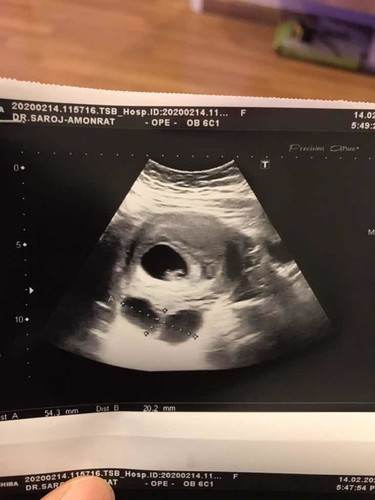

เราท้องได้6w หมอซาวเจอถุงเดียวแต่พอหมอนัดซาวอีกครั้งตอน8w เจอ2ถุงเลย เรากังวลนิดๆกลัวน้องมีผลกระทบ แต่คุณหมอบอกว่าไม่ค่อยอัตรายแต่เราก้อกังวลอยู่ดีค่ะ...

ขึ้นกับว่าเป็นชนิดไหนนะคะ ต้องปรึกษากับหมอค่ะ บางชนิดไม่อันตราย บางชนิดอันตรายค่ะ บ้านนี้เป็นถุงน้ำรังไข่ (ช็อคโกแล็ตซีสต์) ตั้งแต่ก่อนท้องค่ะ หมอที่ศิริราชเชียร์ให้รีบท้อง แล้วพอท้องได้ 3 เดือน มันก็ยุบหายไปหมดเลยค่ะ